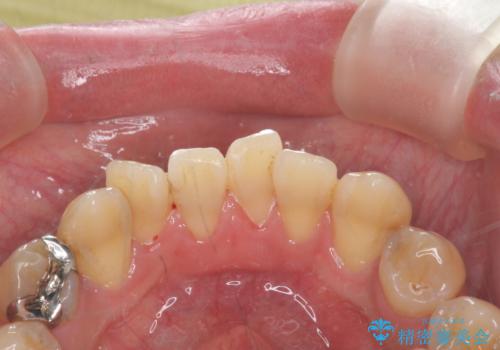

PMTCでコーヒーによる着色を除去。

- コーヒーを毎日飲むため、歯の表面についた着色をとりたいと来院されました。

歯の着色だけでなく、汚れもとれ歯の表面がツルツルになったと

喜んでいただけました。